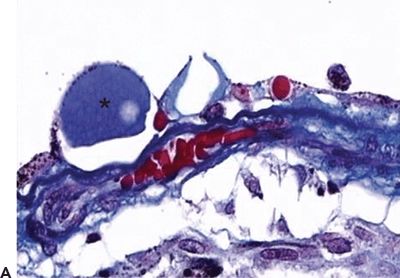

Hard drusen are pinpoint-sized, sharp-edged yellowish retinal lesions easily seen on ophthalmoscopic exam. They are hyperfluorescent in the early stages of the fluorescein angiography and stain late without leakage. Histopathologically, hard drusen are hyaline-like, dense, rounded, homogenous bodies restricted to the basement membrane of the RPE and BM. They consist of a uniform periodic acid-Schiff-positive material and are eosinophilic on the H&E stain (Fig. 5.2A and B) until they start accumulating calcium and consequently become basophilic (16). They also stain lightly positive with special staining technique for lipid (2). On the electron microscopy, they are finely granular or amorphous nodules with similar electrodensity to the basal membrane of the RPE. They may also contain pale vesicles, tubular structures, curly membranes, and wide-banded collagen (15). The overlying RPE is thinned due to degenerative changes as described in Ulshafer et al. (17) electron microscopy studies. There are several hypotheses concerning the formation of hard drusen. Some authors have shown that the main initiating event in their development is the shedding of portions of RPE cells into the BM that are then hyalinized during the apoptosis process (18,19). Others have demonstrated that they are formed by lipidization and degeneration of single cells (20,21). This matter is still uncertain.

Figure 5.2 Histopathologic section of drusen (asterisk) showing atrophy of the overlying pigment epithelium and photoreceptors. A. Masson trichrome digital stain 40×. B. H&E stain 20× (Courtesy Zárate JO, Alvarado M© 2011. Unpublished data.)